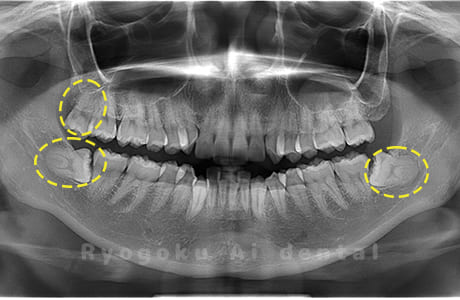

Case03

-

- 原因

- 上顎、下顎の親知らず

- 治療内容

- 上下4本の親知らずを抜歯したケースです。

<リスク・副作用>

手術後は痛み、腫れ、痺れなどの副作用が生じる場合があります。